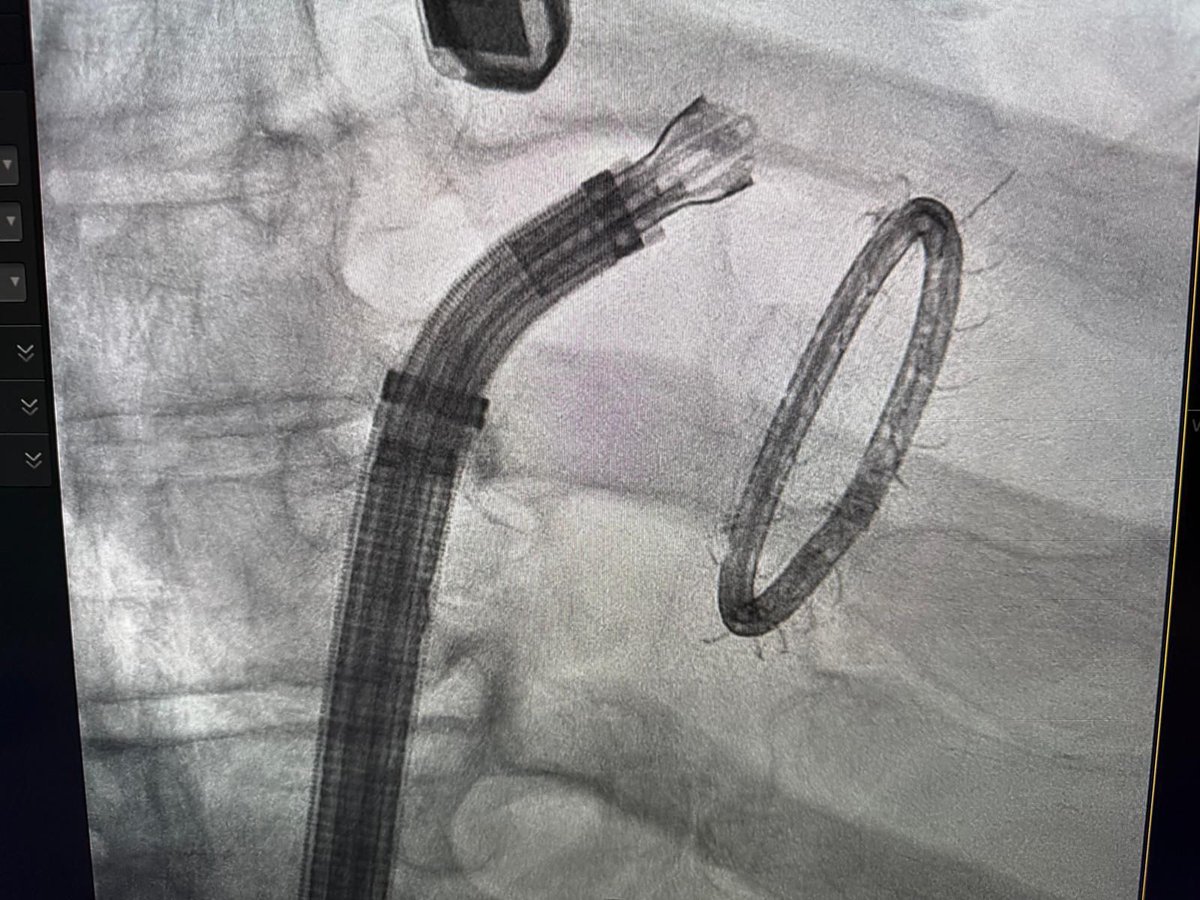

The Effect of Pulmonary Vein Isolation on Gastric Motility: Pulsed-field Ablation vs Radiofrequency